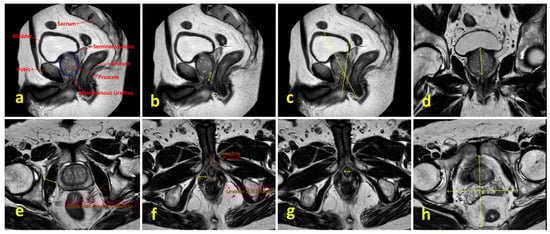

Preoperative PSA levels, age, comorbidities, digital rectal examination findings, BMI, smoking status, lower urinary tract symptoms, sexual function, mpMRI findings, Briganti scores and surgical techniques were examined. Lower urinary tract functions were assessed using the International Prostate Symptom Score (IPSS) form, and sexual functions were evaluated using the International Index of Erectile Function (IIEF-5) form. Patients’ comorbidities were evaluated using the Charlson Comorbidity Index [8]. Preoperative prostate volume, localization and size of the tumor, presence of median lobe, membranous urethra length, membranous urethra–prostate axis angle, obturator internus muscle thickness, levator ani muscle thickness, urethral width, intraprostatic urethra length, adjacent organ invasion, pelvic anterior–posterior and transverse diameters and lymph node positivity were evaluated using mpMRI. The multiparametric MRI parameters of the patients and the measurement of these parameters are shown in Figure 2. Patients were compared in terms of postoperative continence status based on whether nerve-sparing prostatectomy was performed. The nerve-sparing technique was applied according to the previously described ultrapreservation anterior-sparing technique [9] (Figure 3).

Figure 2. Multiparametric MRI parameters of the patients and the methods used for their measurement. (a) Sagittal T2-weighted image showing relevant pelvic anatomical structures. (b) Measurement of membranous urethral length. (c) Measurement of membranous urethra–prostate axis angle. (d) Measurement of intraprostatic urethral length in the coronal plane. (e) Measurement of obturator internus muscle thickness. (f) Visualization of the prostate apex, membranous urethra and levator ani muscle; levator ani muscle thickness is indicated by yellow arrows. (g) Measurement of urethral width. (h) Measurement of pelvic anterior–posterior and transverse diameters.